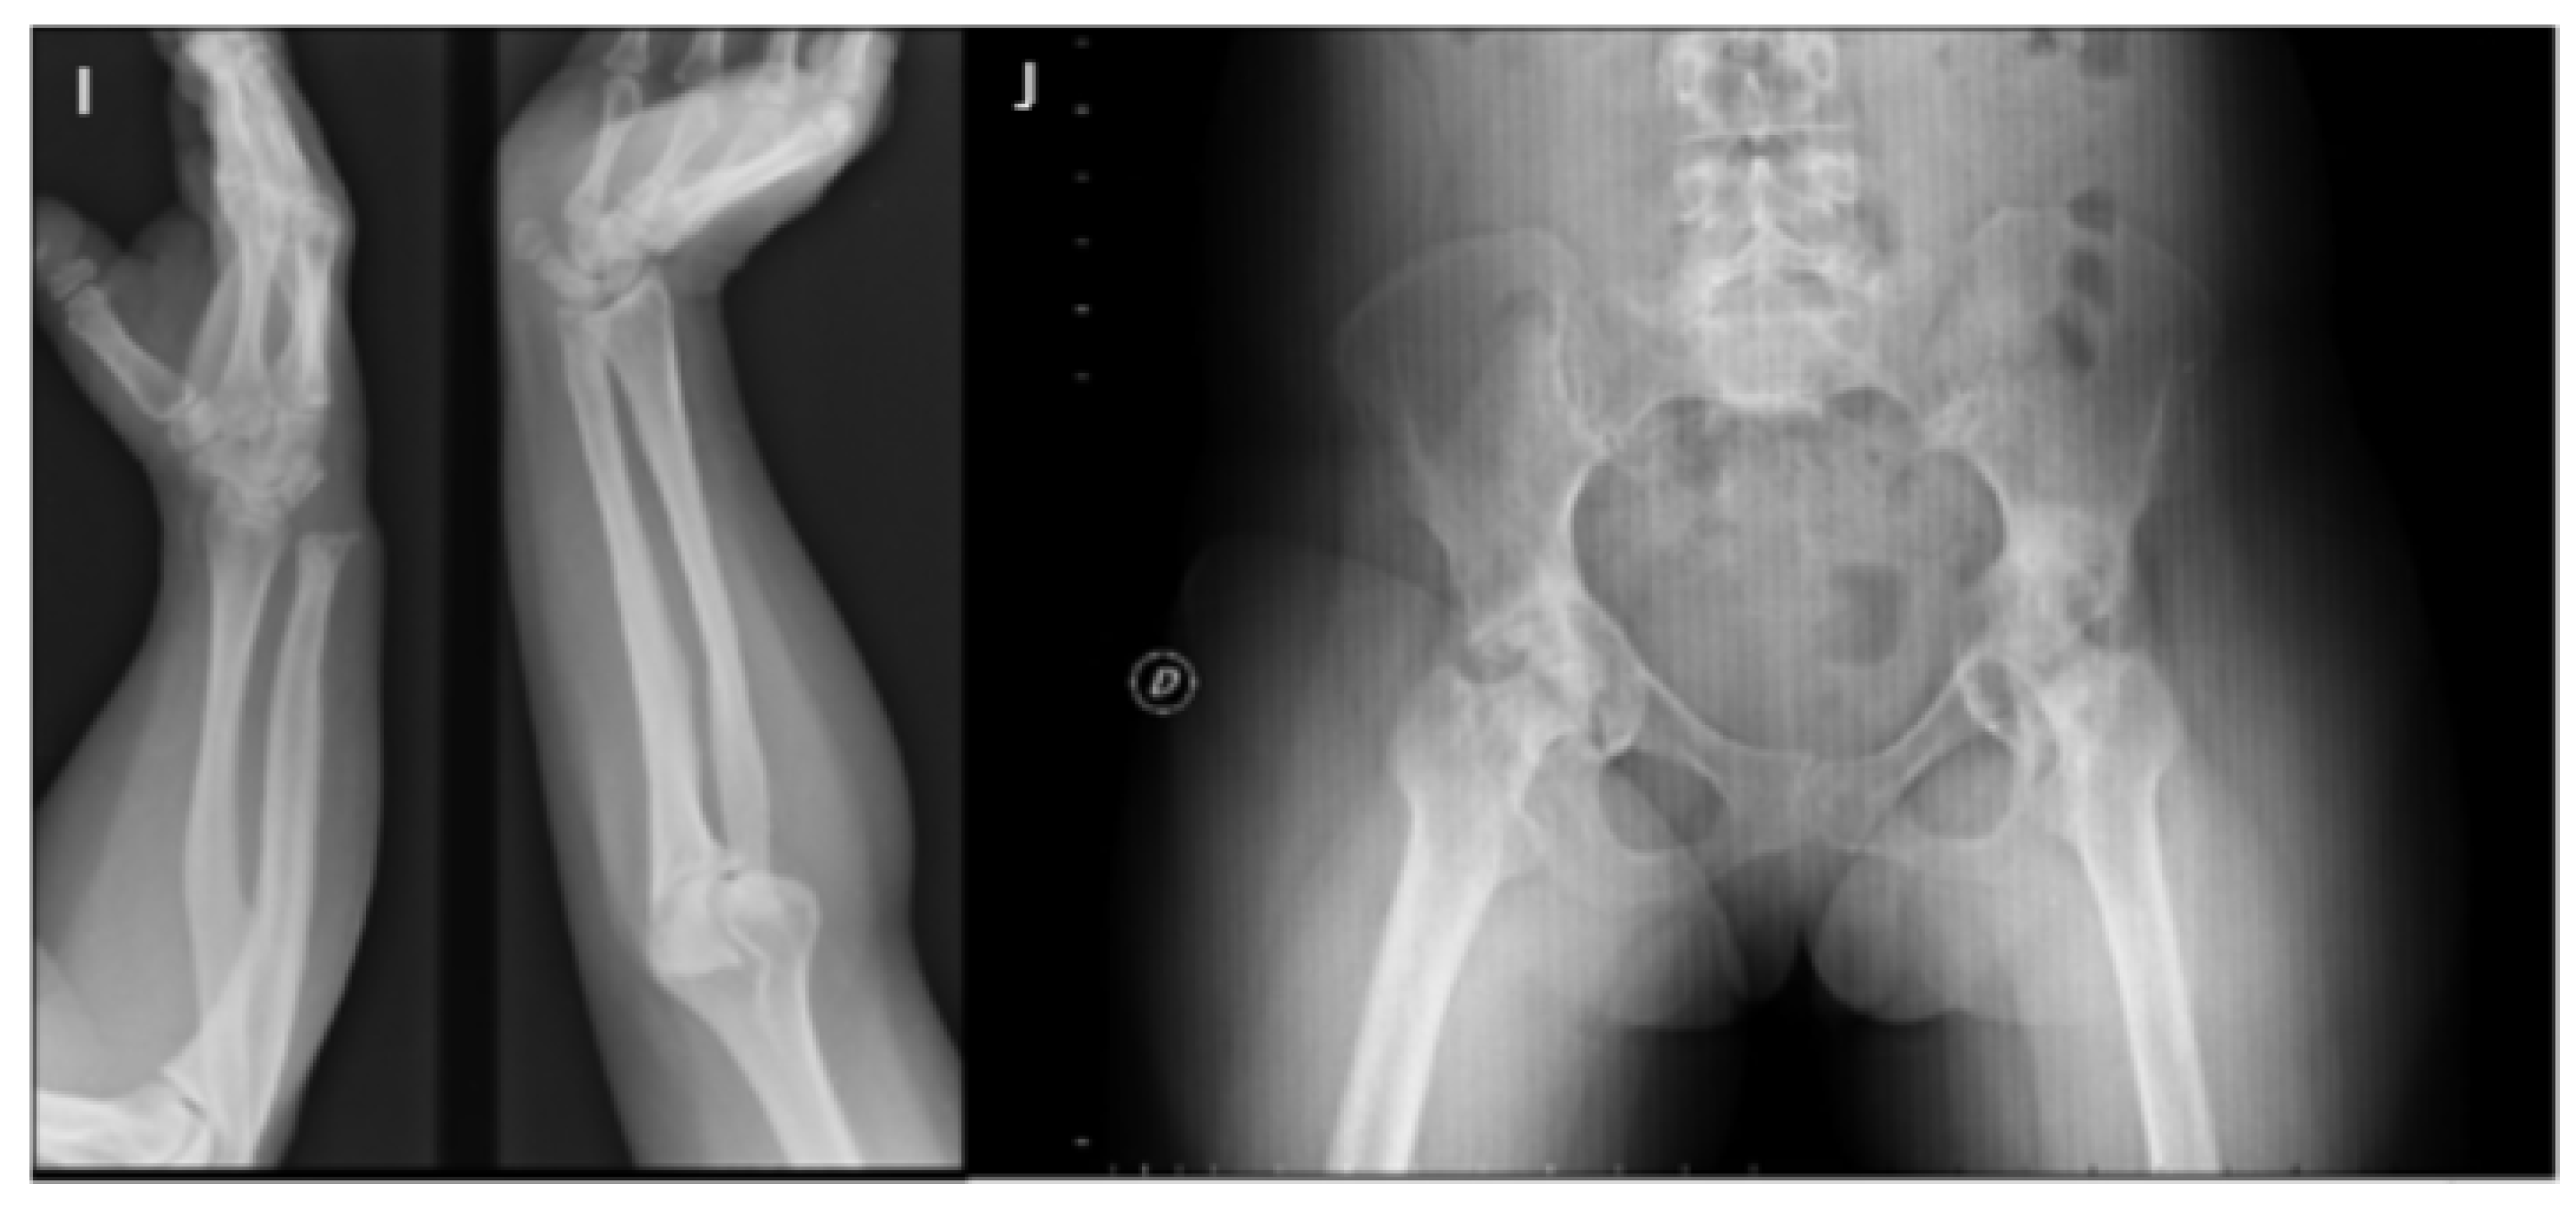

3. Musculoskeletal Features